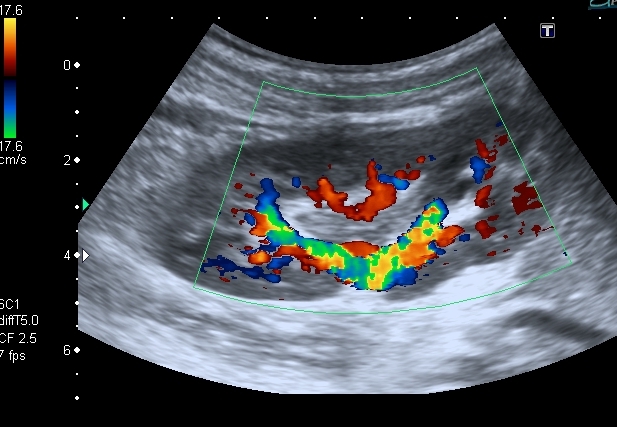

Поэтому правильнее отталкиваться от того что мы видим. А видим мы классические признаки, которые встречаем чаще всего при воспалении ЧЛС - признаки пиелита - признаки отека стенок ЧЛС на фоне воспаления. Здесь аналогичная картина, но, вероятнее всего, вызванная травмой - надрыв - разрыв -нарушение целостности стенки ЧЛС - отек - асептическое воспаление.

По-другому я объяснить изменения пока не могу.

По сему согласен с заключением Др Алекс.

Повреждение паренхимы в данной ситуации присутствует (контузия как минимум), но может быть и разрыв, направленый не наружу, а в сторону ЧЛС.